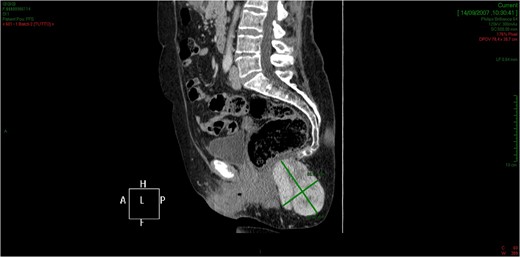

CT showed an hyperintense and inhomogeneous solid lesion taking up the right ischiorectal fossa (maximum diameter of about 10 cm), extended cranially until impressing the wall of the rectal ampulla, with no apparent infiltration (Figs 2 and 3). The lesion presented an intense contrast enhancement, sign of a rich vascularization (Fig. 4).

The lesion extends cranially until impressing the wall of the rectal ampulla, with no apparent infiltration.

The tridimensional reconstruction shows the rich vascularization of the neoplasm.